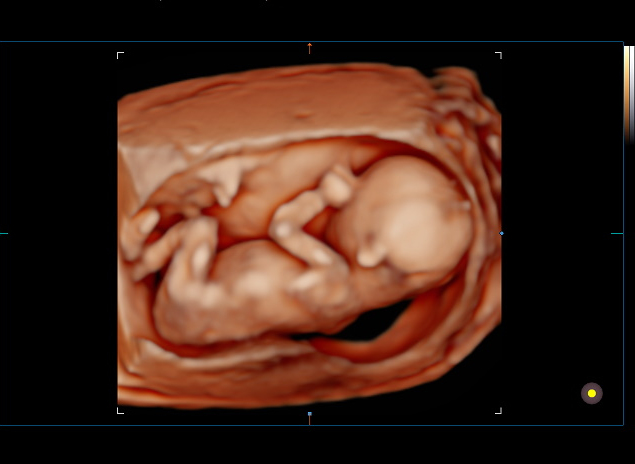

Lumina Ultrasound Boutique is a premier ultrasound studio for expecting parents. We specialize in elective 2D, 3D, and 4D/live motion ultrasound imaging, offering a variety of experiences tailored to the expecting families journey. Whether it’s an early confirmation and peace-of-mind visit, a session designed to capture the perfect 3D image, or a 4D live motion experience to truly bond with their baby, we create meaningful moments that celebrate the joy of pregnancy.

What really sets Lumina apart is that we offer these ultrasound experiences in a cozy, intimate boutique studio, using the latest technology to capture stunning images and videos of baby. Beyond the scans, we provide meaningful keepsakes like heartbeat stuffed animals and jewelry, that let families cherish the sound and image of their baby’s heartbeat for a lifetime. I’ve also carefully curated a selection of natural, non-toxic retail items for both mom and baby, all beautifully handmade in the U.S., so every visit feels thoughtful, personal, and full of special touches.

This is a core memory. It is so special. Mom and her guests should feel deeply connected with their baby in this moment. It should feel perfect in every way. I believe at Lumina, we create this experience. We are more than an ultrasound, we’ve designed an elevated, truly memorable ultrasound experience.